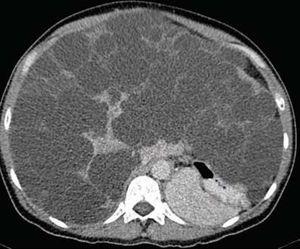

Paciente de 48 años con dolor abdominal en epigastrio, aumento del perímetro abdominal, saciedad temprana, plenitud posprandial y disnea de medianos esfuerzos. El examen físico: T/A: 140/100 IMC: 24.3kg/m², área hepática de 22 cm y hepatodinia. Química sanguínea: Creatinina: 1.06 mg/dL, ALT: 65 UI/L, AST: 28 UI/L, bilirrubina total: 0.67 mg/dL; directa: 0.07 mg/dL. Fosfatasa Alcalina: 60 UI/L.

Ultrasonido y tomografía con evidencia de enfermedad poliquistica del adulto. Se realizó fenestración laparoscopica de los quistes hepáticos, con adecuada evolución.

Figura 3. Quistes hepáticos sin complicación.